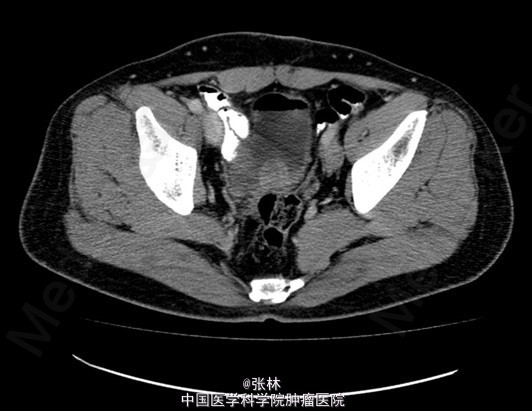

CT:膀胱充盈尚可,内见积气、气液平面;膀胱后壁明显不规则增厚,形成肿物,边界不清,范围约4.8×2.8cm,膀胱壁外缘毛糙,局部与直肠前壁分界不清。考虑:膀胱后壁肿物,与直肠关系密切,考虑为恶性。 MR:膀胱左后壁肿物,与精囊腺及后方直肠分界不清,膀胱充盈状态不同,形态较前改变,现范围约3.6×4.2cm,边界不清楚,T1WI呈低信号,T2/FS呈高信号,DWI扩散受限,增强扫描呈明显不均匀强化,考虑为恶性。